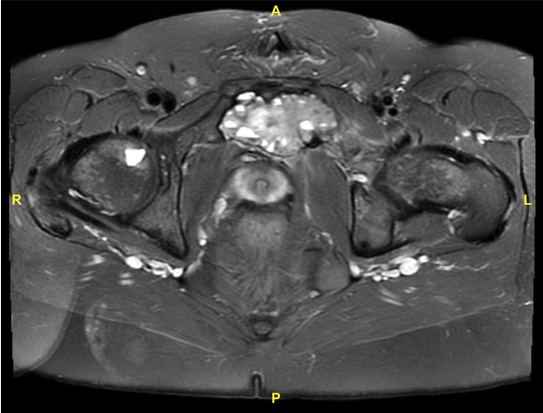

A pelvic radiograph revealed evidence of a destructive mass mostly involving the left superior pubic ramus. Magnetic resonance imaging (MRI) with contrast revealed a low T1 signal intensity and heterogenous T2 hyperintensity 7.5 × 4.9 × 4.3-cm destructive mass in the left superior pubic ramus extending across the pubic symphysis into the right superior pubic ramus with some evidence of fluid-fluid levels (Figure 1). These findings did not definitively rule out malignancy. A needle core bone biopsy demonstrated a variably cellular spindle and round lesion with islands of osteoid formation and focal necrosis. The cells were negative for CD34, S100, and desmin. There was no evidence suggesting osteosarcoma, and final review favored the diagnosis of an ABC. Given the highly destructive nature of the mass, operative resection and curettage was recommended. A multidisciplinary team consisting of orthopedic oncology, plastic surgery, surgical oncology, and urology was assembled to perform the operation.

Figure 1. Preoperative axial T2-weighted MRI delineating the pubic bone lesion.